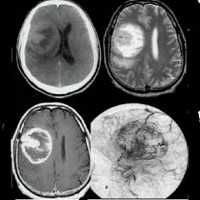

- Магнитно-резонансную томографию. В режиме Т1 опухоль изо- или гиподенсивна, что затрудняет оценку её распространённости. Золотым стандартом диагностики является МРТ в режиме Т2, который даёт гиперденсивную визуализацию глиоматозных зон. КТ головного мозга может не выявить опухолевый процесс, поскольку при данном исследовании глиоматоз оказывается изоденсивным по отношению к нормальным мозговым тканям.

- Компьютерная томография. Выявляет изоденсное церебральное образование с гиподенсным участком центрального некроза, перифокальным отеком, геморрагическим компонентом. Характерен масс-эффект. КТ с контрастированием демонстрирует кольцевое неравномерное окрашивание. Микроскопическая инфильтрация обычно распространяется за пределы визуализируемого очага.

- Магнитно-резонансная томография. МРТ с контрастом гадолиния показывает образование неправильной формы с плотным кольцом усиления, некротизированным центром. Некроз считается отличительной чертой глиобластомы. Также могут визуализироваться окружающий образование вазогенный отек, кровоизлияния, кистозный компонент, искривление или смещение желудочков. Примерно в 13% случаев наблюдается многоочаговость поражения.

КТ может быть нормальной, так как поражения часто изодонны к нормальной паренхиме головного мозга. Относительное отсутствие массового эффекта и искажений по сравнению с масштабностью вовлеченности. Может быть плохо определенная асимметрия или тонкая гипоатенация вовлеченной паренхимы мозга.

МРТ: Масс-эффект и усиление часто минимальны, несмотря на то, что задействованы большие участки головного мозга. Наблюдается потеря дифференциации на серо-белого вещество.